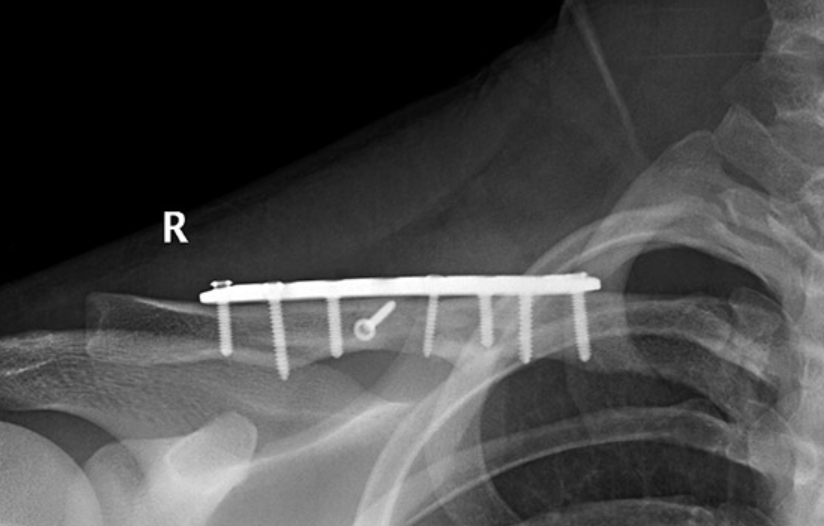

A surgery that stabilizes broken bones using screws, plates, or rods so they heal correctly.

The broken bone is aligned and fixed with metal implants that hold it until it heals naturally.